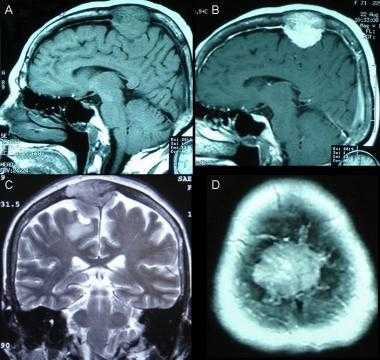

А: на Т1-взвешенном МР-изображении отмечается солидное образование, характеризующееся изоинтенсивностью по отношению к твердой мозговой оболочке, инвазией в кость и сдавлением теменных зон коры.

В: На Т1-взвешенном МР-изображении с контрастным усилением видна частично контрастируемая опухоль.

С: На корональном Т2-взвешенном изображении видно изоинтенсивное образование, что соответствует плотной ткани. Такая картина характерна для фибробластных менингиом.

D : На Т1-взвешенном МР-изображении с контрастным усилением визуализируется гиперинтенсивное образование внутри мозгового вещества кости.